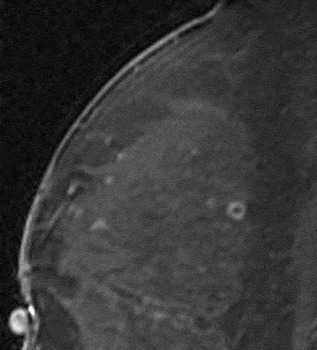

If the mass demonstrates smooth margins and rim enhancement, as rim enhancement is highly predictive of malignancy, biopsy would be recommended in this case as well. Similarly, ductal enhancement that is irregular or clumped will be suspicious for DCIS and biopsy will generally result from this finding. The false positive causes of rim enhancement such as inflamed cyst and fat necrosis have been excluded. Inflamed cysts demonstrate high signal on a T2-weighted sequence. The enhancement of these smoothly marginated, usually round masses, is smooth and quite thick compared to the size of the lesion (Fig. 24). No follow-up is necessary in these cases, as these are benign. Fat necrosis typically demonstrates high-signal fat in the lesion on a non-fat saturated T1-weighted sequence (Fig. 25). Peripheral usually thin rim of enhancement (Fig. 26) may persist for several years. Again, no follow-up is necessary for these lesions.

Figure 24. Inflammatory cyst demonstrating smooth thick rim enhancement. There was a high signal correlate on the T2-weighted sequence.